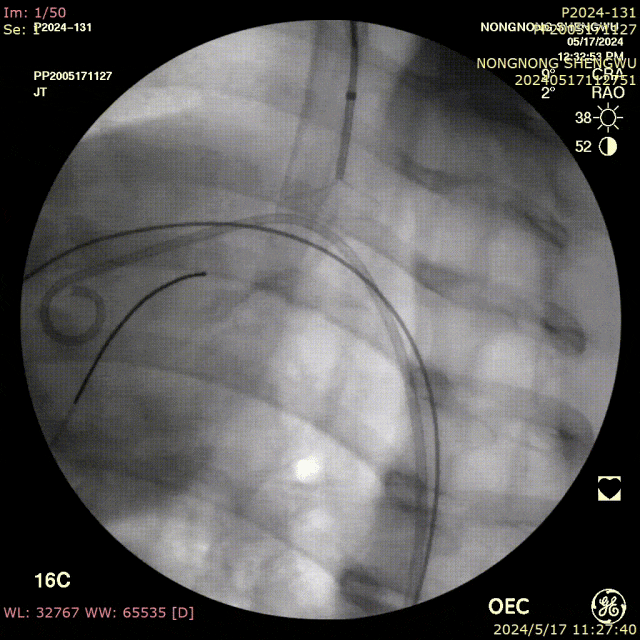

我们在两头35kg巴马公猪中完成动物实验:

成功实现弓上分支的快速、准确原位开窗;

破膜过程流畅,无分支或主动脉损伤;

取出标本可见圆形破口、支架贴合良好,证实技术可行性。

动物实验

巴马公猪35kg